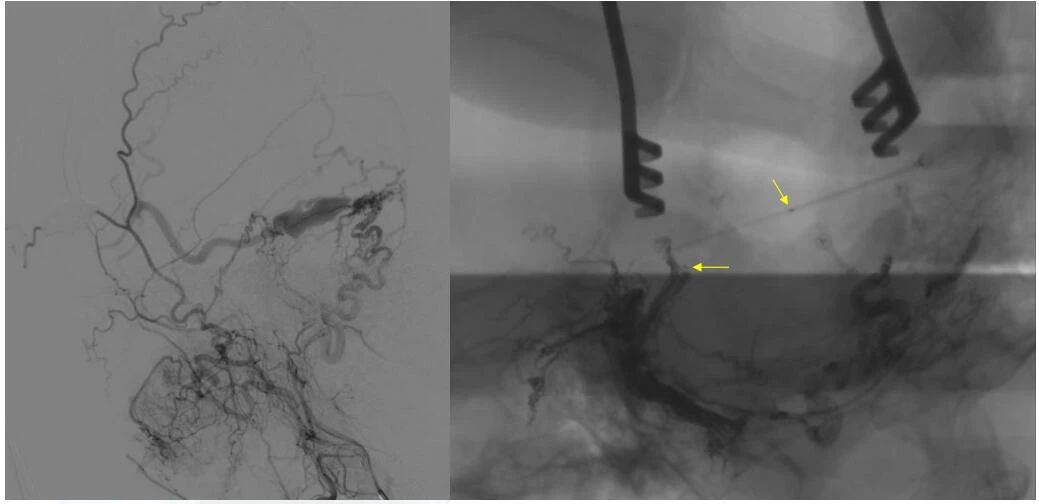

▲ 造影确认位置后,穿刺左侧横窦,置入 Echelon10 微导管

▲ 再次造影确认位置后,填入 HELIX 6/20弹簧圈

经左侧股动脉以单弯造影管超选至左侧颈总动脉造影明确静脉穿刺点入路,予以穿刺针穿刺成功后造影明确在位,随后 Echelon 10微导管到位横窦,填入一枚弹簧圈做塞子,造影明确位置后,缓慢注入 Onxy18胶 5毫升,铸胶弥散良好,通过静脉逆向弥散至部分供血动脉内。复查造影,见瘘口完全被栓塞,引流静脉消失,手术成功。